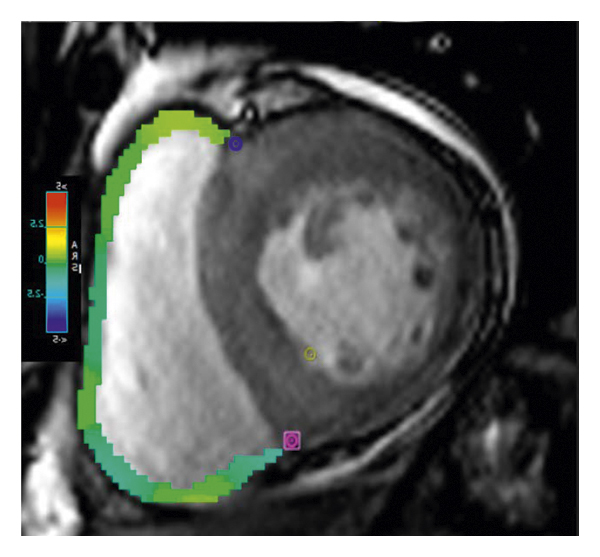

2.3. 이미징 분석모든 이미지 분석은 시중에서 판매되는 소프트웨어(cvi42, Circle Cardiovasic Imaging, Inc. Calgary, Canada)를 사용하여 수행되었습니다. 심장 기능을 측정하기 위해 심장내막 및 심외막 추적을 확장기 말기 및 수축기 말기의 직렬 단축 슬라이스에서 수동으로 수행했습니다. LV/RV 확장기말 용량(EDV), 수축기말 용량(ESV) 및 LV/RV 박출률을 포함한 전체 LV/RV 수축기 기능이 계산되었습니다. LV 및 RV 심근 스트레인 분석은 장축 4챔버 및 단축 슬라이스를 조직 추적 모듈에 로드하여 수행되었습니다(그림 1 (a) 및 1 (b)). RVT는 중실의 3회 측정하였고, 평균 두께를 계산하였다(도 1 (c) 및 1 (d)). GRPS(글로벌 라디칼 피크 변형), GLPS(글로벌 세로 피크 변형) 및 GCPS(글로벌 원주 피크 얼룩)를 포함하여 전역 특징 추적 매개변수가 자동으로 획득되었습니다. 최고 수축기 변형률(PSSR, 이완기부터 다음 수축기까지의 모든 단계에 대한 절대값의 최대 변형률)과 최고 확장기 변형률(PDSR, 수축기부터 다음 수축기까지 모든 단계에 대한 절대값의 최대 변형률)은 다음과 같습니다. 또한 분석했다. 양수 기호와 음수 기호는 서로 다른 동작 방향을 나타냅니다. 앞서 기술한 바와 같이[ 16 ], 정상적인 RVT 값은 7mm 이하로 정의되었다. 기준에 따라 CA 및 HCM 환자를 RV 비대(RVT >7 mm) 또는 RV 비대(RVT ≥7 mm) 환자에 따라 하위 그룹으로 나누었습니다.

(ㅏ) -

(비) -

(씨) -

(디)